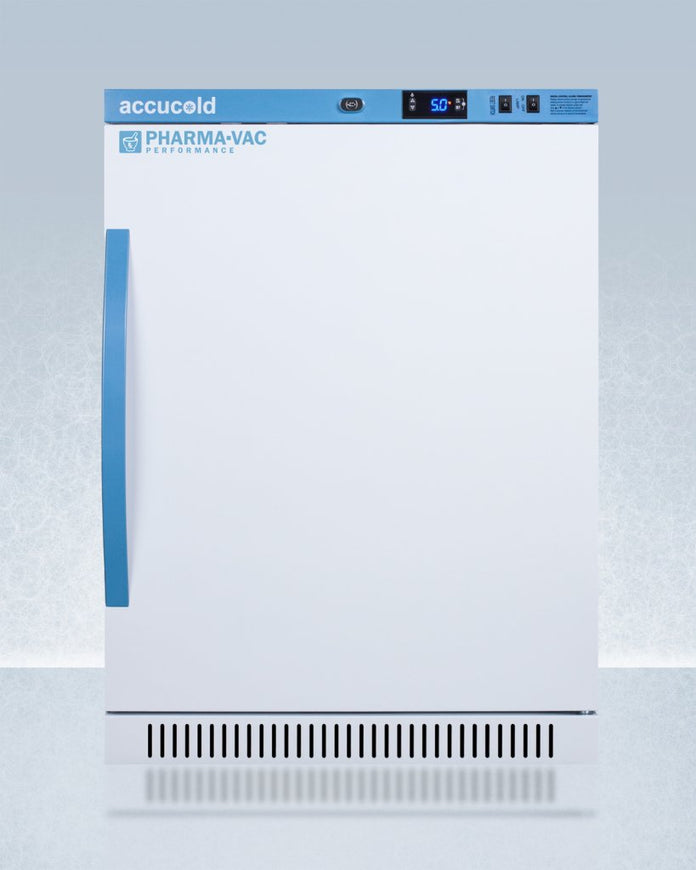

Accucold - ARS6PV-CRT - 6 Cu. Ft. ADA Height Upright Controlled Room Temperature Cabinet

The ARS6PV-CRT is a 6 cu.ft. upright unit pre-set to 72ºF, with an adjustable range from 68º to 77ºF. It is sized at 32.5 inches high for use in most ADA compliant applications. The microprocessor temperature controller is externally located to minimize door openings, helping to protect stored contents from ambient temperature. The buffered temperature probe is encased in a glycol-filled bottle to better simulate temperature of the stored product, with an additional sensor that reads air temperature to ensure superior temperature control. The current and min/max temperature display is viewable in Celsius or Fahrenheit to the nearest tenth of a degree. The audible and visual temperature alarm sounds if the unit's interior goes out of range. Additional alarms include a power failure alert, door open alarm, and sensor failure alarm. This unit is equipped with remote alarm contacts in the rear and a 1/2" probe port on the right side to accept additional monitoring devices. A hospital grade cord with 'green dot' plug is also included for added safety in high traffic areas.

The ARS6PV-CRT comes in a white cabinet finish with a blue accented control panel. The factory-installed antimicrobial handle is powder-coated with naturally occurring silver ions, which help to reduce the spread of germs, allowing for a safer, cleaner user experience. The user-reversible door ships with a right hand swing and self-closing function (note: self-closing is disabled once reversed to LHD). This model includes a factory-installed lock and ships with two keys for staff use. Powerful magnetic gaskets ensure a positive seal.

Designed with hydrocarbon refrigerant, the ARS6PV-CRT provides an energy efficient solution to stabilized room temperature storage, even when ambient temperatures can reach temperatures as cold as 68ºF or warm as 86ºF. This unit is Pyxis, Omnicell, and AcuDose RX compatible. Additional sizes, as well as glass door options, are also available.